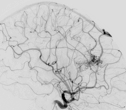

Die Bilder zeigen eine typische AVM und deren erfolgreiche Behandlung mittels Flüssigklebstoff. Es handelt sich um Angiographiebilder, in denen die Blutgefäße des Gehirns durch das eingespritzte Kontrastmittel schwarz dargestellt sind.